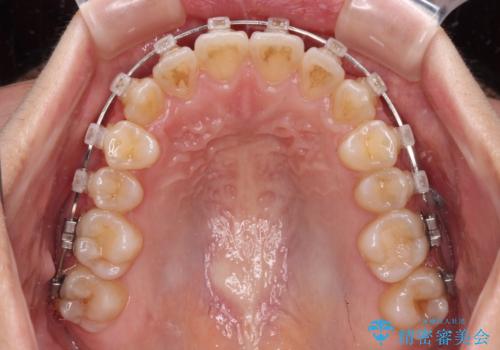

- クリアブラケット

- 1年7ヶ月

- 10-30回

アンカースクリューを用いて、出っ歯仕上がりを回避し、正中位置も改善することができました。